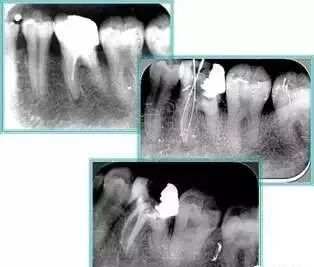

6. 术后 X 线片

术后 X 线片用来评定根管充填 长度、致密度(管壁清晰、侧枝)等指标。

左图为根管充填术后 X 线片。图中可见,根管充填较好。右下图有白色小点,为侧方加压导致糊剂挤出所致,表明根管充填比较致密。

致密、恰到好处的充填可去除干净根管里感染灶,机体逐渐恢复。

多根牙时候需进行偏移投照,正位投照无法说明具体哪根牙根管充填效果。